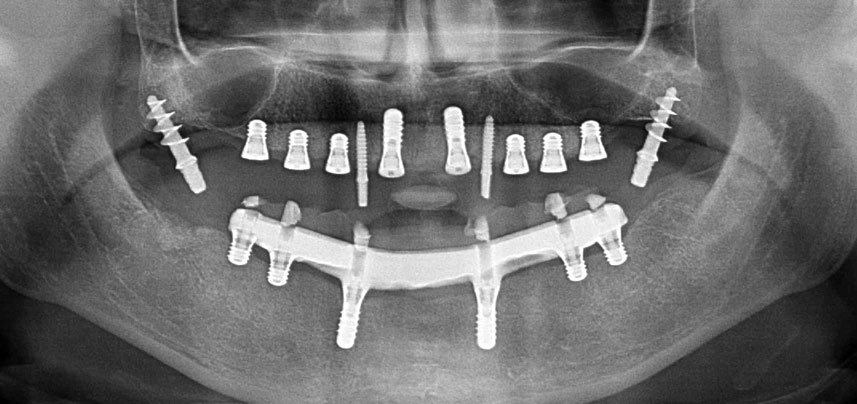

Radio panoramique post-opératoire

Fig. 10 : La radio panoramique post-opératoire montre que tous les implants sont à leur place, y compris les implants provisoires tubérositaires.